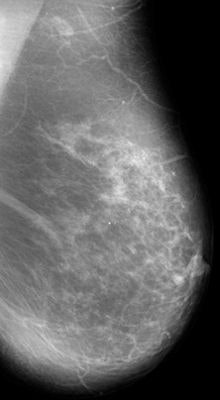

In a new 16-year study, Spanish researchers have found that switching to full-field digital mammography (FFDM) leads to early diagnosis, not overdiagnosis. The group found that cancer detection rates did not increase when compared with film-screen mammography, but going digital did lead to an increase in ductal carcinoma in situ (DCIS) detection rates.

Some observers fear that switching to FFDM increases the negative effects of screening through overdiagnosis, or the detection of cancers that may not pose a health hazard to patients in their lifetime. The new research shows, however, that DCIS detection is higher with FFDM than with analog mammography, and there is also a trend to identify less advanced invasive cancers. The results mean two things: either there's an improvement in early diagnosis with FFDM, or there's an increase in overdiagnosis.

The researchers included 82,961 film-screen and 79,031 FFDM studies acquired in women ages 50 to 69 who were screened biennially from 1995 to 2010 in Spain and followed up to 2012. Rates of cancer detection, interval cancer, tumor characteristics, and other quality indicators were compared between the analog and digital periods.